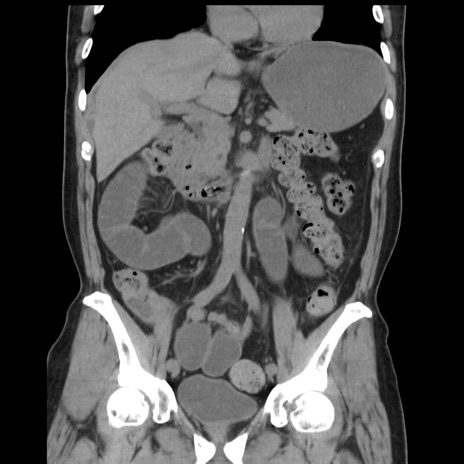

症例16(冠状断像)

【症例】 70歳代男性

【主訴】 腹痛、嘔吐

【現病歴】 約1ヶ月前より間欠的に腹痛と嘔吐あり、当院消化器内科を受診したところCTで多発する肝臓のLDAを指摘され、精査中であった。以降は消化器症状は安定していたが、2日前より嘔気と腹痛があり、同日より排便・排ガスが消失した。改善認めず、 本日、救急外来を受診した。